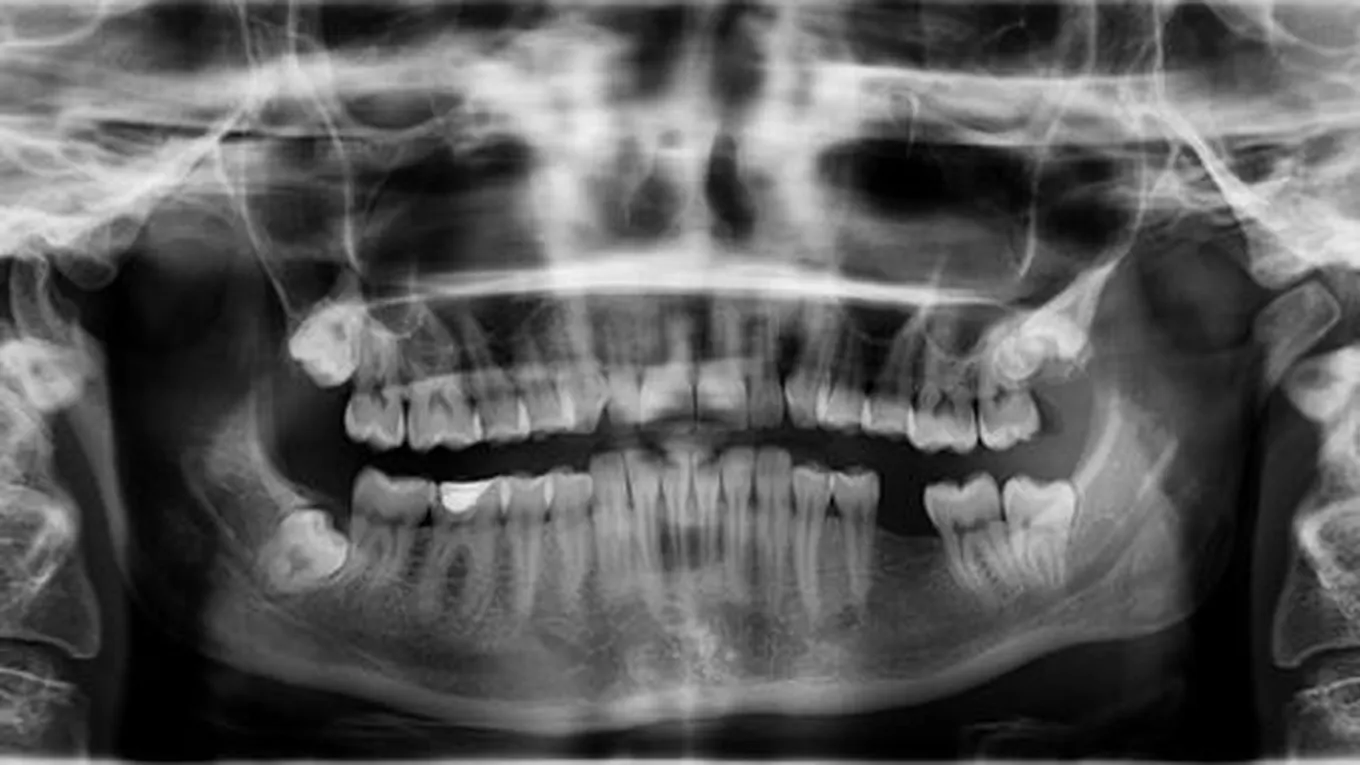

هنالك العديد من الفوائد والوظائف التي يحملها ضرس العقل، بحيث تعود على الإنسان بالنفع، وخصوصاً إذا نمت تلك الأضراس في الوضع الطبيعيّ، وليس بشكلٍ مائل أو أفقي، حيث يمتلك كلّ إنسانٍ أربعة أضراس عقليّة، إثنان منهما في الفكّ العلوي، واثنان في الفكّ السفلي، فقد أثبتت الدراسات أن خلع ضرس العقل السليم والخالي من التسوّس والمشاكل، يؤدي إلى حدوث مضاعفات جانبيّة كبيرة، كما أنها تؤثر على سلامة الأسنان وصحتّها، وهنا سيخطر ببالنا هذا السؤال، ما فائدة ضرس العقل:

يؤدّي ضرس العقل إلى العديد من المشاكل لدى بعض الأشخاص، وخصوصاً إذا ظهر بصورةٍ غير طبيعيّة، كأن ينمو بشكلٍ أفقيٍ أو مائلٍ، ومن هذه المشاكل ما يلي: